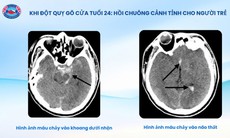

Đột quỵ ngày càng trẻ hóa

Một thực tế đáng lo ngại khác là xu hướng trẻ hóa của bệnh đột quỵ đang ngày càng rõ rệt, không còn là căn bệnh "của người cao tuổi" như trước đây.

Thực tế lâm sàng ghi nhận không ít trường hợp bệnh nhân đột quỵ ở độ tuổi rất trẻ, thậm chí chỉ ngoài 20. Điều này không chỉ ảnh hưởng đến sức khỏe cá nhân mà còn kéo theo nhiều hệ lụy về kinh tế, xã hội khi người bệnh đang ở độ tuổi lao động, học tập.